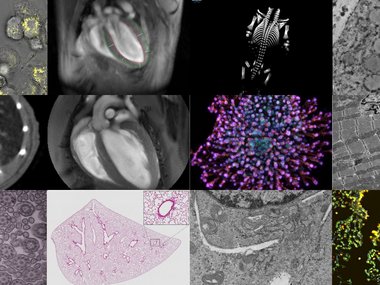

Scientific Service Groups

In order to achieve excellent research results, not only outstanding scientists are needed, but also an efficient system of scientific services that specifically support the work of the departments with state-of-the-art technologies. At the Max Planck Institute for Heart and Lung Research in Bad Nauheim these are the service groups: